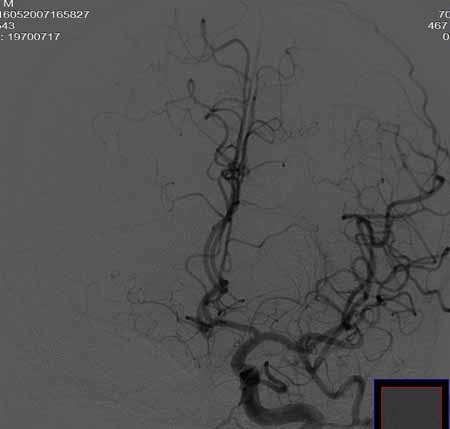

右侧颈总动脉闭塞(血栓形成),左侧大脑前动脉侧支、前交通动脉供应右侧大脑半球

右侧颈总动脉闭塞 ,左侧大脑前动脉侧支、前交通动脉供应右侧大脑半球,后交通部分开放 。缓慢代偿血流,分级3

右侧颈总a闭塞,右颈内颈外未显影,左侧未见异常,并通过wills环代偿右侧大脑半球血供